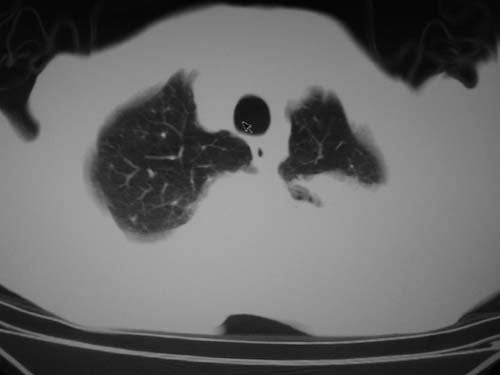

标题: CT19736:男,76岁,咳嗽,胸痛 [打印本页]

标题: CT19736:男,76岁,咳嗽,胸痛

支持左上肺周围型肺癌性并空洞形成伴胸椎转移。

左上沟癌空洞形成并胸椎转移。

考虑癌性空洞并胸椎转移。

空洞内壁有多发结节,支持癌性空洞。

支持左上肺周围型肺癌并空洞形成伴胸椎转移。z左下肺炎

左上肺癌性空洞伴胸椎转移。